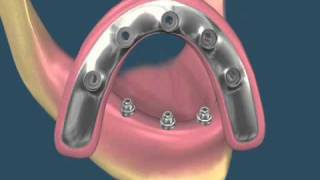

Perguntas frequentes sobre Implantodontia

1. Quanto tempo preciso ficar afastado do meu trabalho para fazer os implantes? A cirurgia de implantes normalmente tem um pós-operatório...

10 MOTIVOS PARA FAZER UM IMPLANTE DENTÁRIO

1 – Autoestima O motivo que leva muitas pessoas a buscarem um tratamento de implante dentário: Perder um dente tira a autoestima de...

Diga adeus as dentaduras, ponte-móveis e ponte-fixas - Implantes Dentários a solução

Medo de Implante? Entenda o que é e como funciona! Cada dia mais procurados, os implantes devolvem, literalmente, o sorriso dos...